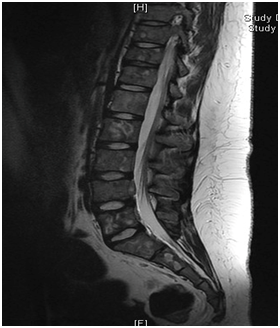

A 9-year-old Saudi boy presented to the emergency department complaining of pain in his ankles, with a history of trauma and difficulty walking. He had this trauma one month before reporting to the hospital and was described as trivial by parents. The patient had no history of fever and no change in his weight. On examination, he was afebrile. Neurological exam was normal but he was unable to walk. The X-ray radiograph showed that the posteromedial part of the distal metaphysis of the left tibia had an abnormal configuration with an irregular margin. Furthermore, as shown in Figures 1 & 2, there was a decrease in tibio-talar joint space bilaterally and a general decrease in bone density. Investigations showed the following values: platelet count: 91; an absolute neutrophil count: 0.2; hemoglobin: 9; and WBC: 2000. Vitamin D, calcium, and bone marrow aspiration tests revealed a marked decrease in the vitamin D level and a 97% blast in the bone marrow, as shown in Figure 3. Flow cytometry showed positivity for CD19, CD22, CD33, CD34, CD10, CD79a, TdT, CD11b, and HLA-DR. The patient was put on chemotherapy, Tazocin, cotnmoxazol, nystatin, and sodium bicarbonate. Thereafter, his lower limb pain significantly improved and he started to walk normally.

Figure 1 Anteroposterior view.

Figures 1 & 2 Posteromedial part of the distal metaphysis of the left tibia with abnormal configuration and irregular margin.